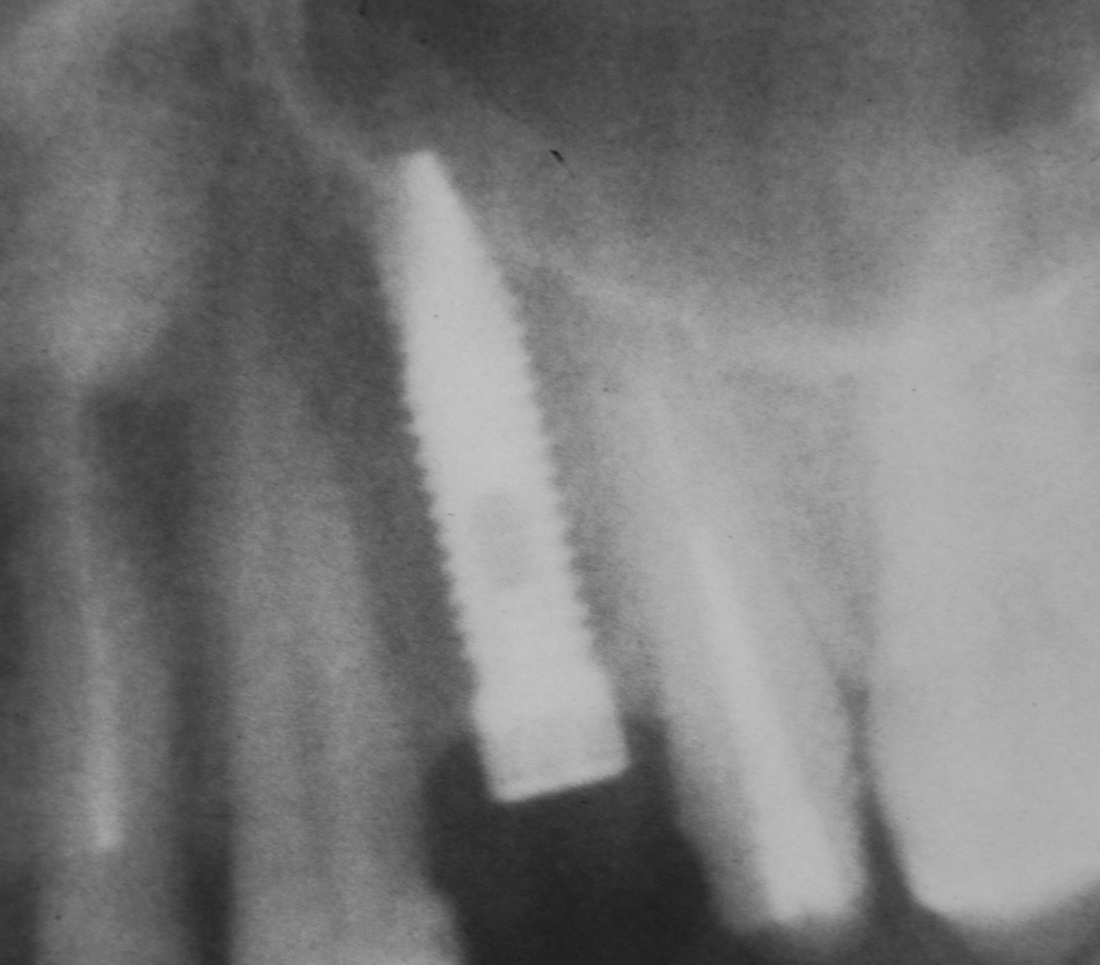

Для этого мы сделали КЛКТ:

И КЛКТ показала нам, что с имплантатами и окружающей костью всё зашибись. Через 12 лет после операции, отсутствия наблюдения, пофигизма в замене временных коронок! Нужны ли тебе еще какие-нибудь доводы в пользу долгосрочной эффективности метода?

Серия контрольных снимков на этапах: